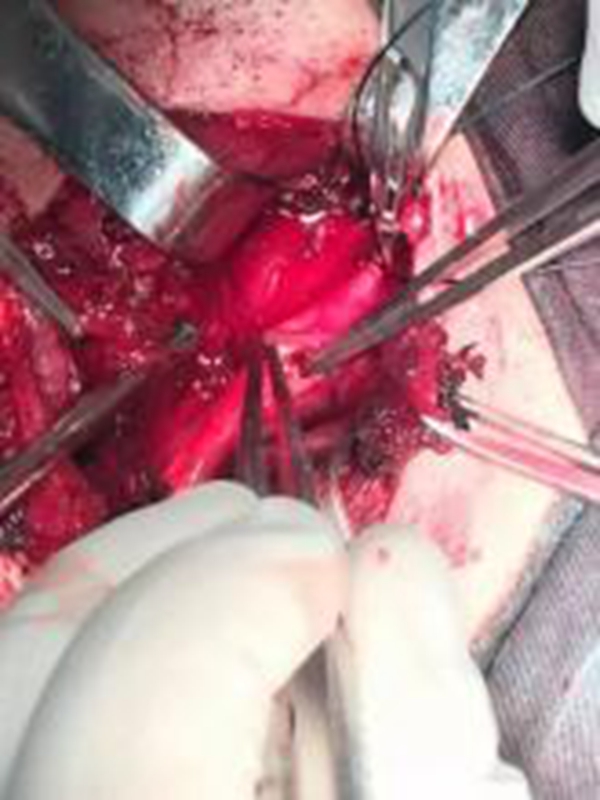

幼兒煙霧病腦手術

幼兒頸部手術煙霧病

幼兒頭部手術煙霧病

A:煙霧病目前有兩種手術方式,分別是血管搭橋手術和血管貼敷手術。血管搭橋手術是將顳淺動脈進行剝離,然後與大腦中動脈進行吻合搭橋。而血管貼敷手術是將顳淺動脈剝離後貼敷到腦的表面上。通過這兩種手術方式,主要的起到的作用是建立新的側枝循環,從而供應腦……